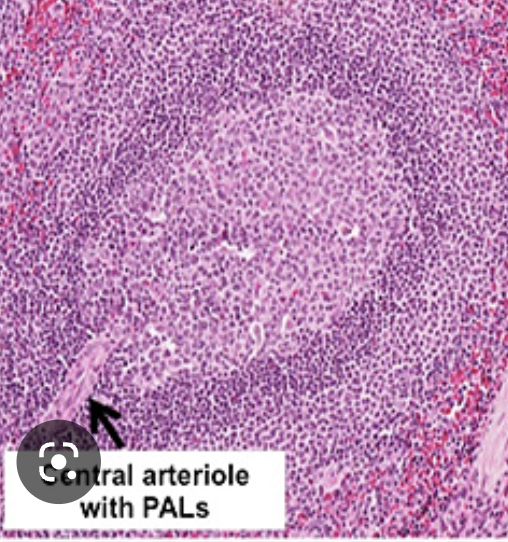

what is this

A

white pulp of slpeenm

white pulp in the spleen

immunological -white cells